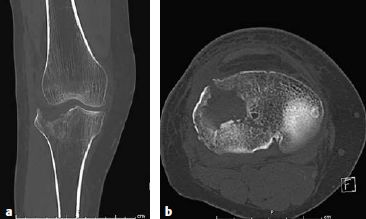

外侧柱骨折由伸膝‑外翻暴力造成,因此后续的复位和支撑固定必须防止外翻畸形的再发生。推荐采用前外侧入路。单纯劈裂型骨折(41B1.1)可以通过拉力螺钉、支撑钢板或更常用的二者之联合来进行固定。劈裂合并塌陷型(41‑B3.1)是指外侧柱骨折合并关节面塌陷,完善的术前检查(例如,CT扫描)是精确评估关节面损伤的关键(图6.8.1‑20),将塌陷的骨块复位后,克氏针临时固定有助于稳定关节面,骨折的最终固定最好使用钢板,拉力螺钉可以单独或者经钢板联合应用。

图6.8.1-20 a-d

a  CT冠状位图像显示外侧平台的劈裂-塌陷骨折;b  CT横断位显示外侧平台前外侧关节面的严重缺失;c-d  三维CT图像